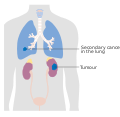

سرطان الكلية

| Kidney cancer | |

| الأسماء الأخرى | Renal cancer |

| Micrograph showing the most common type of kidney cancer (clear cell renal cell carcinoma). H&E stain. | |